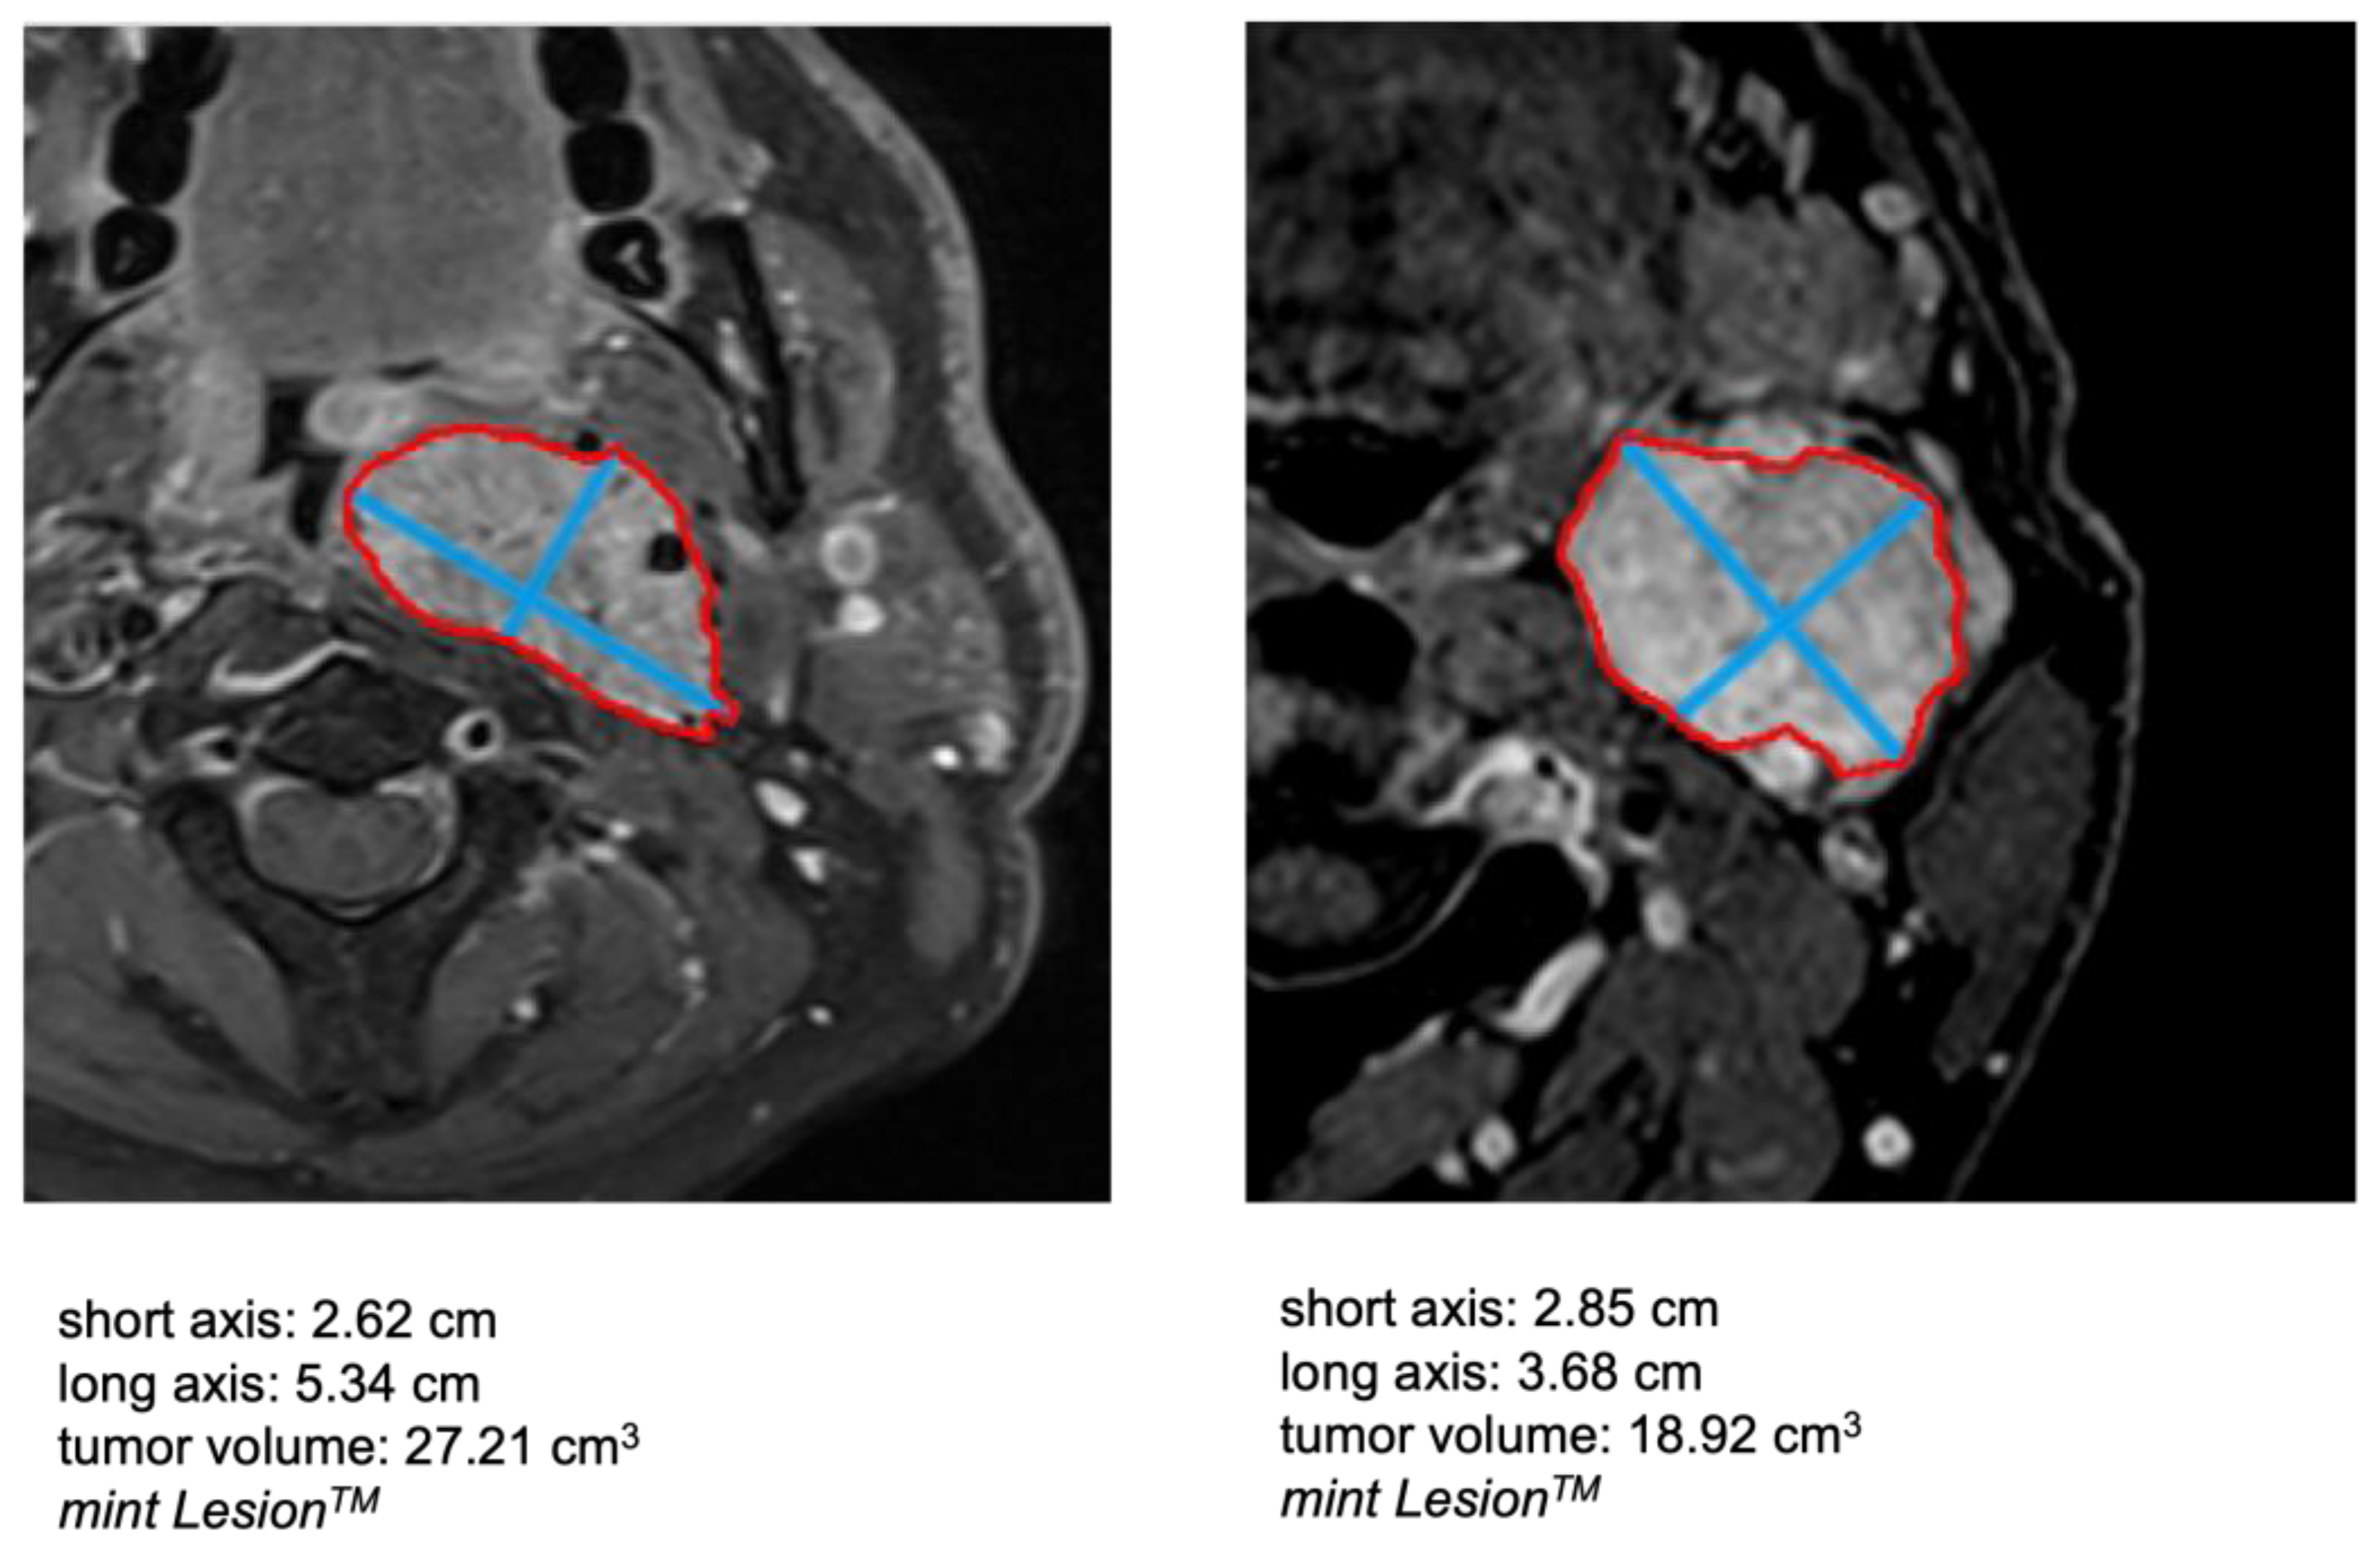

2.3. Image Analysis